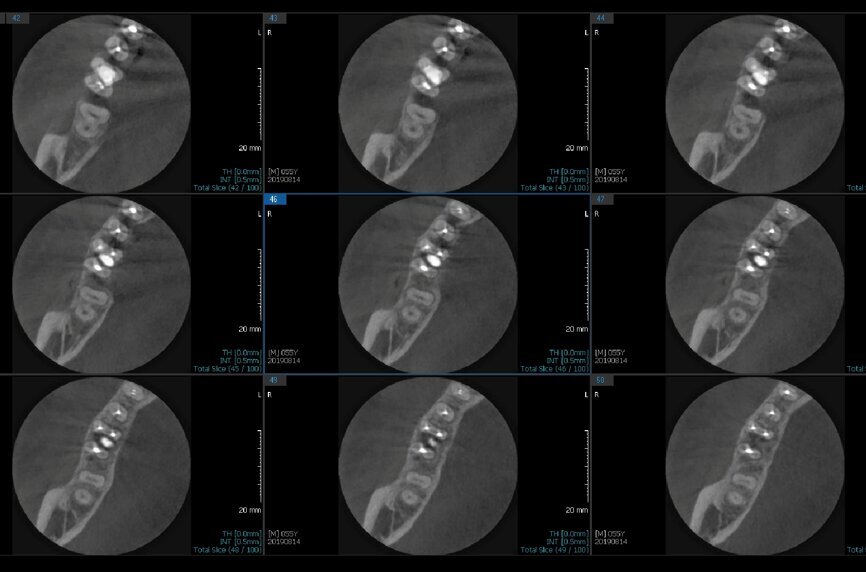

Fig.2a: Pre-op CBCT images of tooth #46: No obturation material in the distal and mesiobuccal canal (a); scanty obturation of the canals and breach of the floor of the pulp chamber, no obturation beyond a few millimetres down the orifice (b & c); radiolucency in the furcation area and periapical region of both roots (d -g).

Fig.2b: Pre-op CBCT images of tooth #46: No obturation material in the distal and mesiobuccal canal (a); scanty obturation of the canals and breach of the floor of the pulp chamber, no obturation beyond a few millimetres down the orifice (b & c); radiolucency in the furcation area and periapical region of both roots (d -g).

Fig.2c: Pre-op CBCT images of tooth #46: No obturation material in the distal and mesiobuccal canal (a); scanty obturation of the canals and breach of the floor of the pulp chamber, no obturation beyond a few millimetres down the orifice (b & c); radiolucency in the furcation area and periapical region of both roots (d -g).

Fig.2d: Pre-op CBCT images of tooth #46: No obturation material in the distal and mesiobuccal canal (a); scanty obturation of the canals and breach of the floor of the pulp chamber, no obturation beyond a few millimetres down the orifice (b & c); radiolucency in the furcation area and periapical region of both roots (d -g).

Fig.2e: Pre-op CBCT images of tooth #46: No obturation material in the distal and mesiobuccal canal (a); scanty obturation of the canals and breach of the floor of the pulp chamber, no obturation beyond a few millimetres down the orifice (b & c); radiolucency in the furcation area and periapical region of both roots (d -g).

Fig.2f: Pre-op CBCT images of tooth #46: No obturation material in the distal and mesiobuccal canal (a); scanty obturation of the canals and breach of the floor of the pulp chamber, no obturation beyond a few millimetres down the orifice (b & c); radiolucency in the furcation area and periapical region of both roots (d -g).

Fig.2g: Pre-op CBCT images of tooth #46: No obturation material in the distal and mesiobuccal canal (a); scanty obturation of the canals and breach of the floor of the pulp chamber, no obturation beyond a few millimetres down the orifice (b & c); radiolucency in the furcation area and periapical region of both roots (d -g).

When I had a close look at the preoperative radiograph from the referring dentist (Fig. 1a), I observed that there was insufficient obturation of the mesial canals and almost no obturation of the distal canal. Both roots displayed periapical radiolucency. The clinical examination revealed a Grade I mobility, and the tooth was tender to percussion. The periodontal examination ruled out any pockets and loss of attachment. We took an intra-oral periapical radiograph (Fig. 1b), from which we observed the loss of coronal structure and a large radiolucent area over the furcation area and the periapical area of both the mesial and the distal roots. A CBCT scan of tooth #46 was advised to check for any details that may have been missed in the intra-oral periapical radiograph (Figs. 2a–g). From the CBCT scan, it could be observed that there was inadequate obturation of the distal canal on the horizontal plane, no obturation beyond the middle third in the mesial canals and a breach of the floor of the pulp chamber. The questionable prognosis was explainedto the patient, and written consent was obtained.